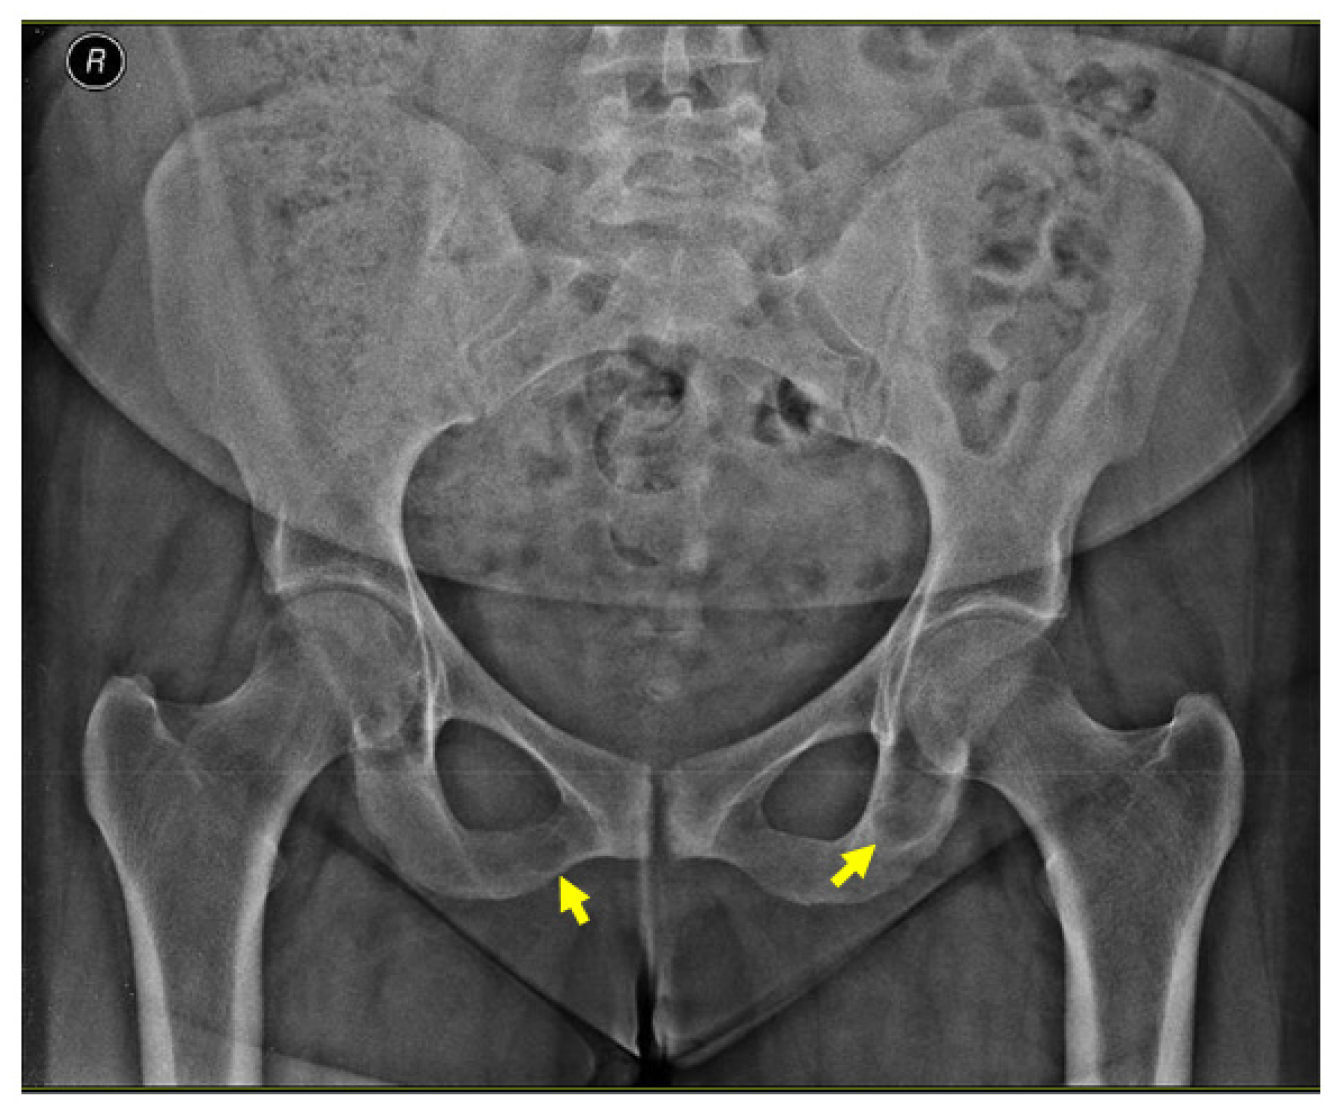

An X-ray of the pelvis also revealed multiple osteolytic lesions of the ischium (brown tumor features) with normal femoral head sphericity and position and a mildly reduced coxo-femoral joint space (Figure 4).

Figure 4.

X-ray of the pelvis: brown tumors at the level of the ischium (yellow arrows).

A pelvis CT scan confirmed the osteolytic lesions of the ischium and of the left coxal bone adjacent to the acetabular fossa, measuring 1.97 by 3.29 cm and 1.14 by 1.71 cm, respectively (brown tumors) (Figure 6).

Figure 6.

Pelvis CT scans showing other brown tumors: (A) osteolytic lesion of the left coxal bone adjacent to the acetabular fossa of 1.14 by 1.71 cm (axial plane); (B) osteolytic lesion of the left ischium of 1.97 by 3.29 cm (axial plane).